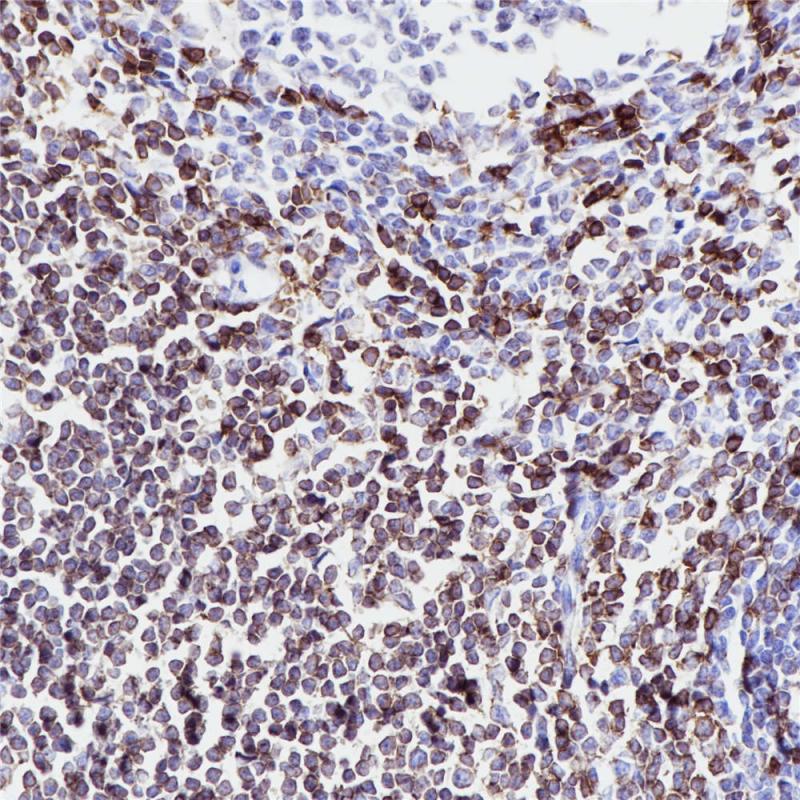

CD5 重组兔单克隆抗体

CD5抗原分布于分布于大多数T 细胞及胸腺细胞(95%)及多数T细胞淋巴瘤。套细胞淋巴瘤和慢性B淋巴细胞白血病和小淋巴细胞淋巴瘤也可阳性,而滤泡性淋巴瘤、毛细胞白血病、大细胞淋巴瘤等为阴性。此抗体有助于对B细胞淋巴瘤进行分类,并且可能有助于区分胸腺癌和肺癌。

阳性对照

阑尾

亚细胞定位

细胞膜